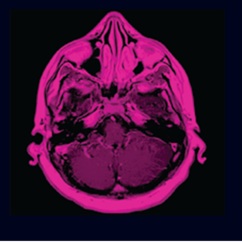

Encefalitis equina del oeste: formas de presentación en resonancia magnética

revisión del tema a propósito de una serie de casos en Uruguay

Kevin Schenck, Nadia Vanoli, Liliana Servente, Nicolás Sgarbi

61-66